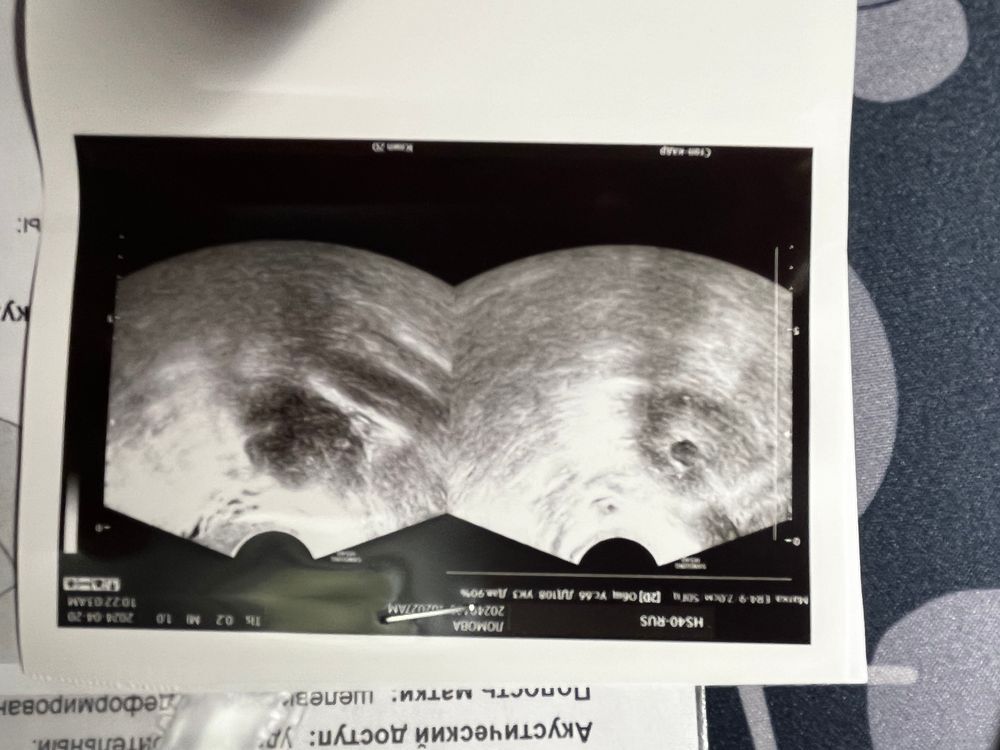

Это 21 дц с фолликулами до 10 шт в двух яичника Изображение ИзображениеА это 31 дц, где в девлм один а правый пустой Изображение